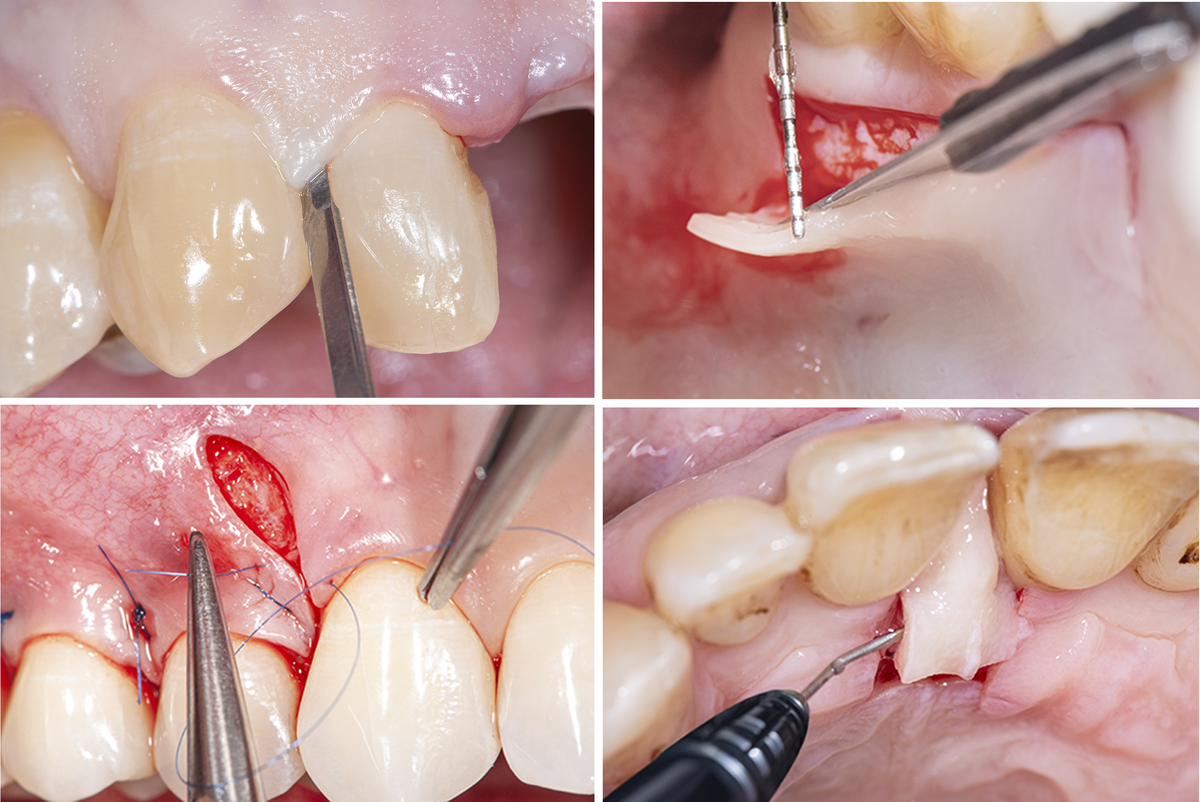

According to the scientific literature, these factors include various surgical factors—such as incision technique, surgical flap type and thickness, tension-free surgical flaps, the volume of augmentation materials, the amount of tissue trauma caused by the procedure—as well as the manual dexterity of the surgeon.

The quality of surgical soft-tissue management plays a decisive role in this context. Careful preoperative planning of all aspects of the procedure from the initial incision to flap preparation, flap mobilization, and flap stabilization is imperative. Measures to maintain the best-possible blood supply to the surgical area and to achieve the highest-possible wound stability are the focus of these efforts (Figure 2).